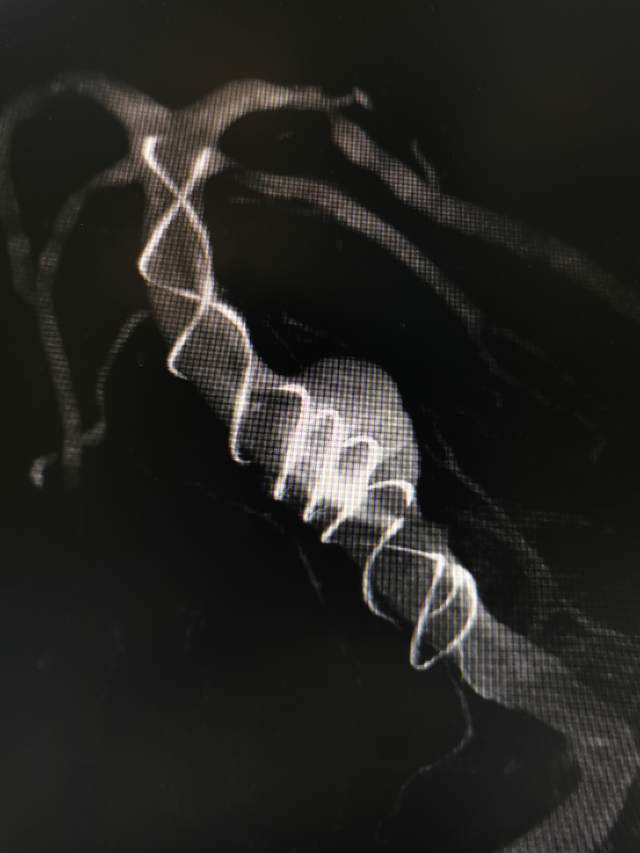

患者男性,34岁,年前自新疆坐车48小时来到我院,诊断:椎基底动脉冗长扩张症,出现脑干压迫症状、后组颅神经症状、部分中组颅神经症状、小脑症状、颅内压增高(220mmHg),症状进行性加重,最大径15mm,血管外面存在血栓造影只能窥见部分,短短两周,病变形态出现明显变化,局部出现明显瘤样凸起(图2-3),手术方案只能临时改变,植入血流导向装置,术后看病人语言、四肢活动均正常,围手术期仍然是一个艰巨的过程,充满了不确定因素,希望患者能安全度过围手术期,早日康复,重返工作岗位~~~